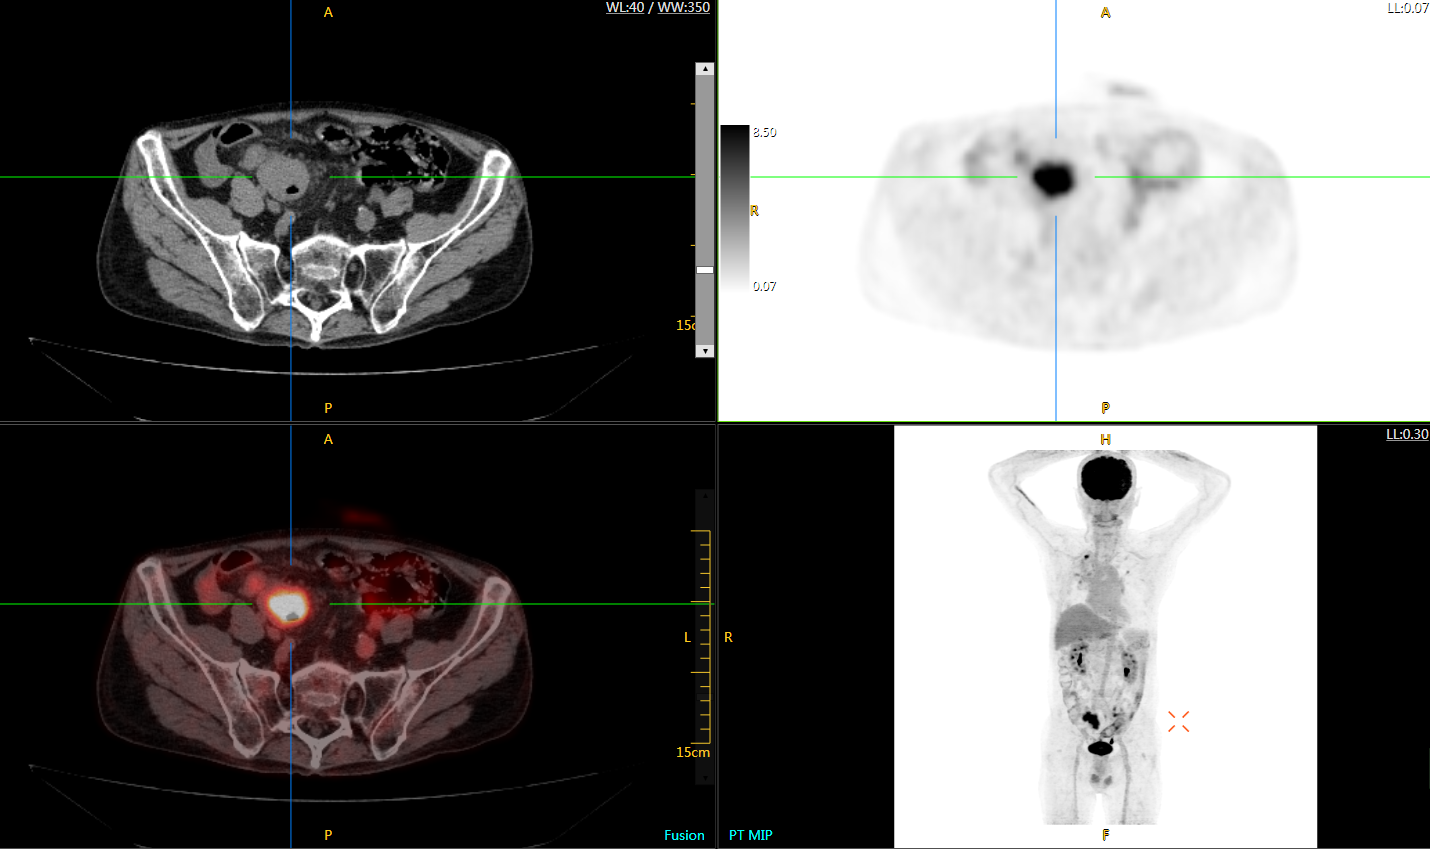

直腸癌

男,45歲,直腸癌術(shù)后9個月,發(fā)現(xiàn)肺占位

臨床診斷:直腸區(qū)術(shù)后改變,復(fù)發(fā)伴骶骨受累,雙肺多發(fā)轉(zhuǎn)移